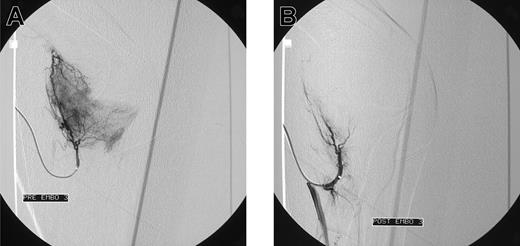

Blush in a patient with elbow bleeding. Angiogram shows massive blush in a patient with recurrent spontaneous elbow bleeding before (A) and after (B) embolization.

Initial angiograms demonstrated a blush, indicative for hyperemic tissue as cause of bleeding in 15 patients (Figure 1A-B); in 2 patients a false aneurysm was observed (Figure 2A-B); in one patient a true aneurysm was observed; and in 3 patients an arteriovenous shunt in combination with an aneurysm was observed. In all these cases embolization of the feeding arteries was performed. However, in some cases, it was not possible to embolize all the bleeding arteries. In 2 patients, the cause of bleeding could not be localized (one patients with postoperative knee bleeding and one with spontaneous elbow bleeding) and embolization was not performed.